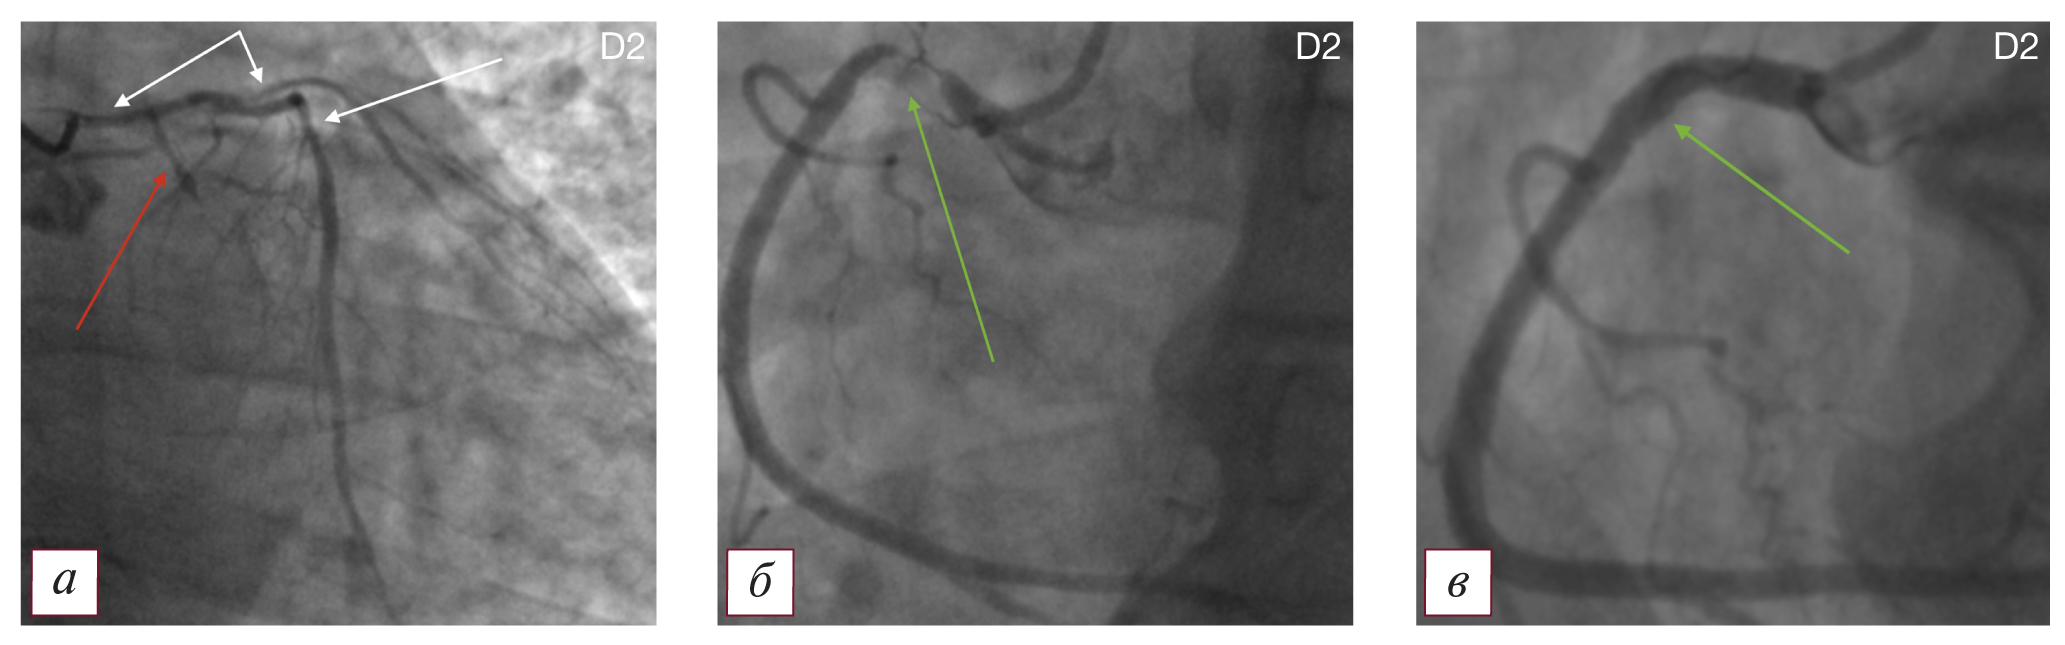

Tип D2 — ПАЛЖ в сочетании с гемодинамически значимым поражением крупной коронарной артерии в зоне аневризмы и единичным гемодинамически значимым поражением правой коронарной артерии при правом типе кровоснабжения миокарда (рис. 2).

Рис. 2. Коронароангиографическая картина поражения коронарного русла и постинфарктной аневризмы левого желудочка по типу D2: а — гемодинамически значимый стеноз ствола левой коронарной артерии 70%, эшелонированные стенозы передней нисходящей артерии до 70%, субокклюзия устья 1-й диагональной ветви (указаны белыми стрелками); окклюзия проксимальной половины огибающей артерии (указана красной стрелкой); б — дискретная субокклюзия проксимальной трети правой коронарной артерии (указана зеленой стрелкой); в — правая коронарная артерия после выполнения первого этапа лечения — стентирования проксимальной трети (зона стентирования указана стрелкой). / Fig. 2. Coronary angiographic picture of the lesion of the coronary bed and postinfarction aneurysm of the left ventricle according to type D2: a — hemodynamically significant stenosis of the trunk of the left coronary artery 70%, echeloned stenosis of the anterior descending artery up to 70%, subocclusion of the mouth of the 1st diagonal branch (indicated by white arrows); occlusion of the proximal half of the envelope artery (indicated by red arrow); б — discrete subocclusion of the proximal third of the right coronary artery (indicated by the green arrow); в — the right coronary artery after performing the first stage of treatment — stenting of the proximal third (the stenting zone is indicated by an arrow).